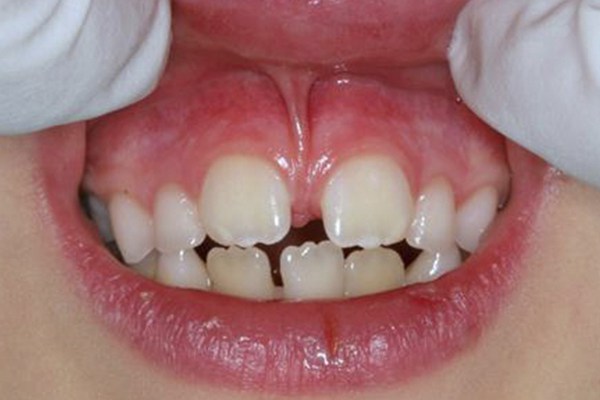

- frenectomias;